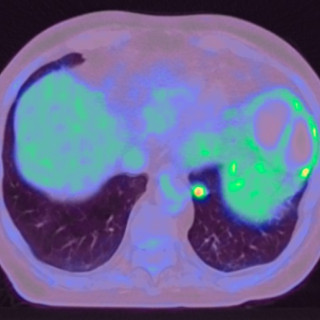

En mann i 50-årene ble brakt bevisstløs til akuttmottaket, hvor det ble påvist forhøyet osmolalt gap og aniongap. Pasientens promille på 2,1 kunne forklare det forhøyede osmolale gapet, men neppe bevisstløsheten eller det økte aniongapet. Årsaken til bevissthetstapet ble påvist først fire timer etter innleggelse, og det kliniske bildet var atypisk. En mann i 50-årene ble funnet bevisstløs utendørs. Ambulansen ankom fire minutter etter varsling, og pasienten hadde da GCS-skår (Glasgow Coma Scale) på 3, snorkende respirasjon, normal respirasjonsfrekvens (18 pust/min) og ikke målbar SpO 2. Han...